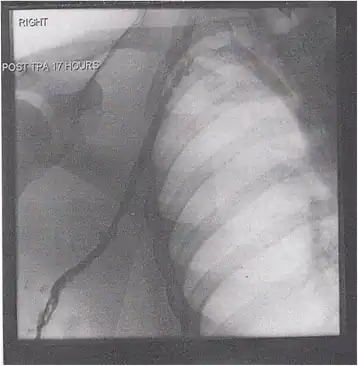

Thrombolysis is the injection of an enzyme into the veins to dissolve blood clots, and while this treatment has been proven effective against the life-threatening emergency clots of stroke and heart attacks, randomized controlled trials[139][140][141] have not established a net benefit in those with acute proximal DVT.[5][142] Drawbacks of catheter-directed thrombolysis (the preferred method of administering the clot-busting enzyme[5]) include a risk of bleeding, complexity,[l] and the cost of the procedure.[125] Although, while anticoagulation is the preferred treatment for DVT,[125] thrombolysis is a treatment option for those with the severe DVT form of phlegmasia cerula dorens (bottom left image) and in some younger patients with DVT affecting the iliac and common femoral veins.[12] Of note, a variety of contraindications to thrombolysis exist.[125] In 2020, NICE kept their 2012 recommendations that catheter-directed thrombolysis should be considered in those with iliofemoral DVT who have "symptoms lasting less than 14 days, good functional status, a life expectancy of 1 year or more, and a low risk of bleeding."[138]

A mechanical thrombectomy device can remove DVT clots, particularly in acute iliofemoral DVT (DVT of the major veins in the pelvis), but there is limited data on its efficacy. It is usually combined with thrombolysis, and sometimes, temporary IVC filters are placed to protect against PE during the procedure.[143] Catheter-directed thrombolysis with thrombectomy[141] against iliofemoral DVT has been associated with a reduction in the severity of post-thrombotic syndrome at an estimated cost-effectiveness ratio of about $138,000[m] per gained QALY.[144][145] Phlegmasia cerulea dolens might be treated with catheter-directed thrombolysis and/or thrombectomy.[19][143]

A venogram before catheter-directed thrombolysis for Paget–Schroetter syndrome, a rare and severe arm DVT shown here in a judo practitioner, with highly restricted blood flow shown in the vein -

After treatment with catheter-directed thrombolysis, blood flow in the axillary and subclavian vein was significantly improved. Afterwards, a first rib resection allowed decompression. This reduces the risk of recurrent DVT and other sequelae from thoracic outlet compression.[147]